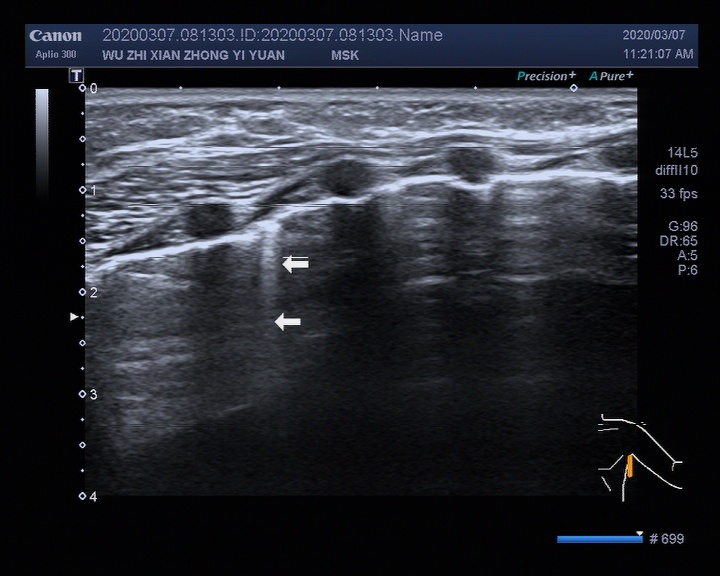

▎5个月婴儿肺脏超声检查超声图像

image013

image015

左腋前线、腋中线2-4肋间可探及散在B线